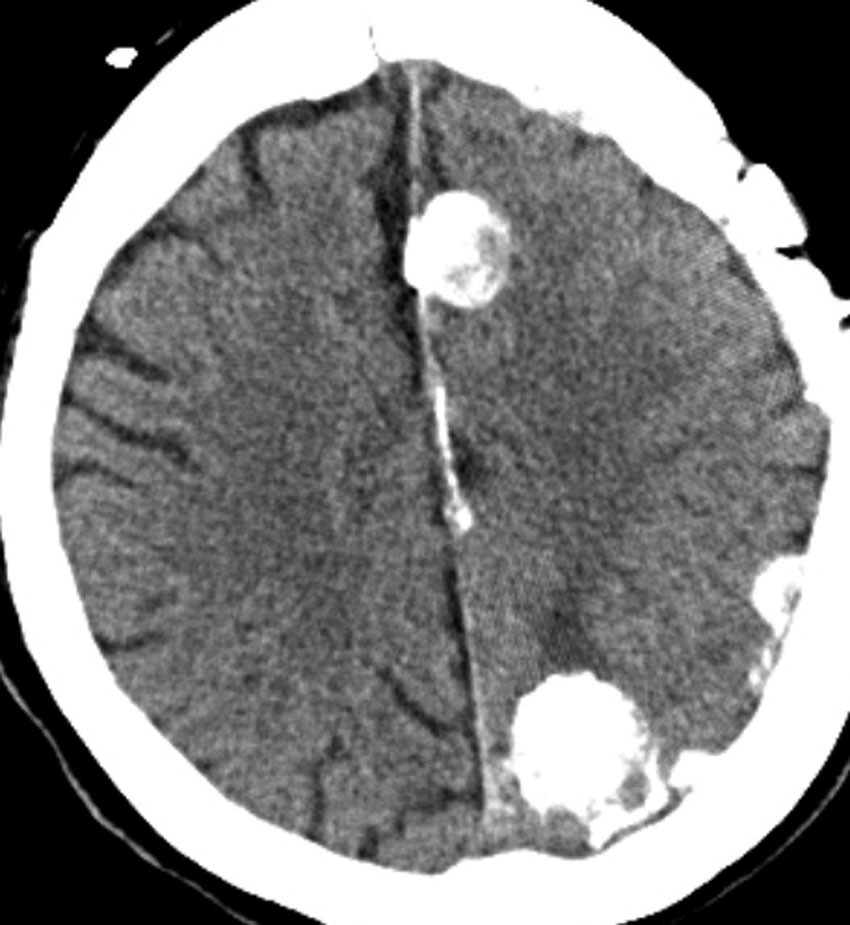

多発例,NF-2ではないもの

30代で下肢の局所てんかん発作で発見されました。テント上硬膜の腫瘍化です。数えれば総数で30個以上はあったでしょう。このタイプは手術で硬膜を広範囲切除(ほとんど全頭蓋冠)することで治すことができます。

H字状皮膚切開で広範囲両側前頭登頂開頭をして,穹窿部と傍矢状洞部髄膜腫をほとんど摘出してしまいました。上矢状洞は開存していたので残してあります。